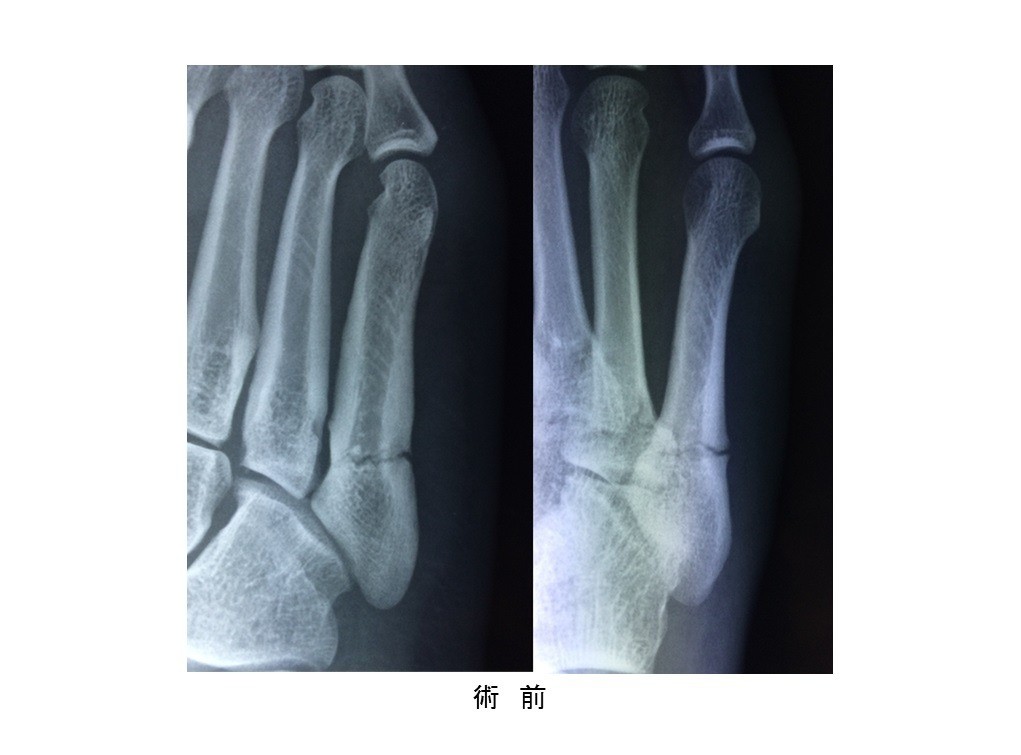

• 第5中足骨骨折(ジョーンズ骨折)

スポーツ整形

第5中足骨骨折(ジョーンズ骨折)